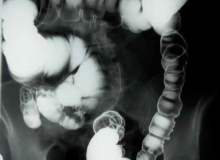

İğne biyopsisi, laboratuar testi için vücudunuzdan hücre örnekleri alınması işlemidir. Yaygın iğne biyopsisi işlemleri, ince iğne ile çekmeyi ve core needle biyopsisi olarak adlandırılan bir parça doku alınmasını kapsar. İğne biyopsisi kaslar, kemi